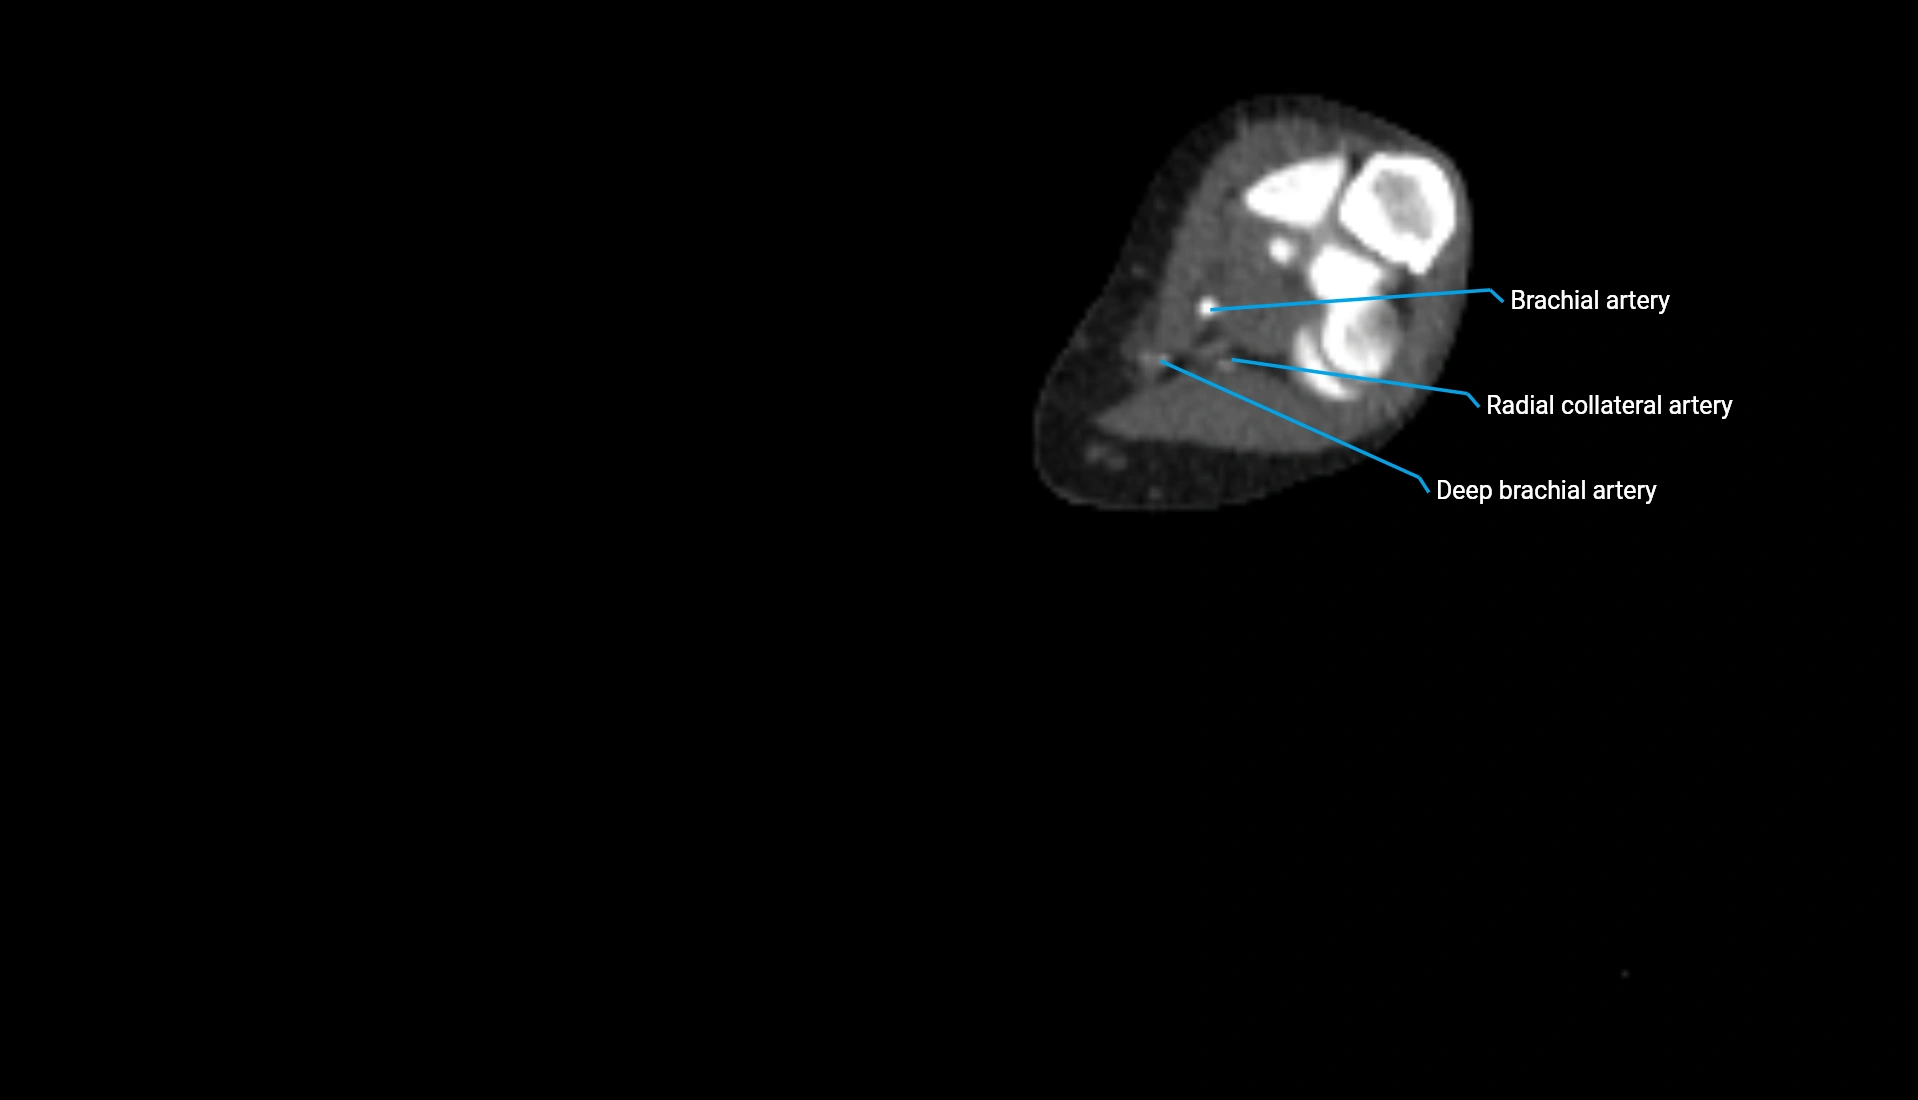

CT Appearance

Non-Contrast CT:

• Cortex: High-density, sharply defined

• Subchondral bone: Dense cancellous matrix

• Articular surface: Smooth concave contour articulating with the capitellum

• Excellent for evaluating bone integrity, alignment, and subtle fractures